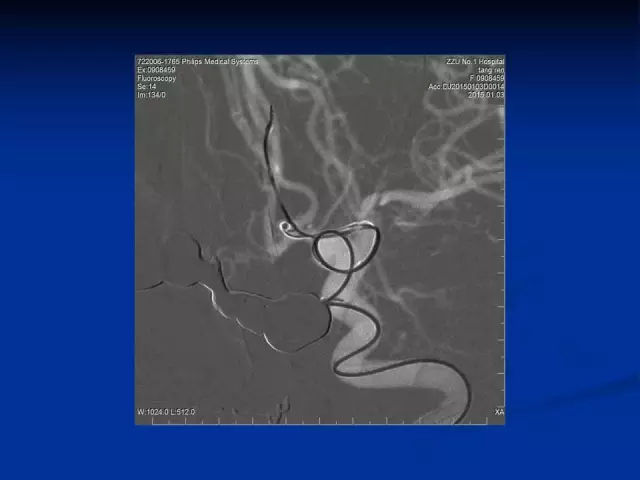

管生教授:Enterprise支架临床应用现状